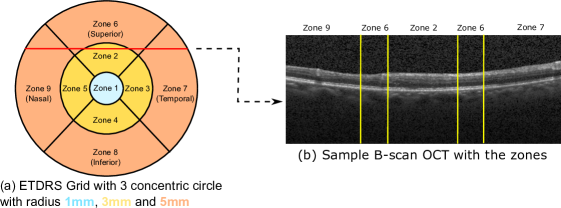

Given a retinal OCT volume acquired for a specific subject, the thickness of the overall retina is generally reported as an Early Treatment of Diabetic Retinopathy Study (ETDRS) grid, providing the average thickness in 9 different spatial zones of the retina [29]. The spatial zones are centered at the fovea and are delineated as shown in Figure 8. The severity of an edema is assessed based on the thickness of these spatial zones by assessing deviations from normal ranges. As the Duke SD-OCT dataset does not contain the local anatomical information (left / right eye) and annotations are made by sparsely sampling the OCT along the azimuthal direction, we assume all the image volumes are aligned left to right with the temporal to nasal axis in our evaluation. The azimuthal resolution of the frames varies between 118118118-128μ128𝜇128\mum. We assume it as 122μ122𝜇122\mum for placing it in the grid. It must be noted that due to this assumption, the computed chart is not exact but does show its potential use for computing the grid provided exact resolutions are known. We compute the overall retinal thickness by combining the delineated retinal layers and report the mean absolute difference in overall retinal thickness for the different comparative methods at each of the spatial zones in Table 5. We observe that the performance of ReLayNet is significantly better than all the comparative methods for all the 9 zones. Zone 1 indicating the foveal region (most clinically significant) has an very low error of 0.3 pixels. CM-Unet has the second best performance for 4 out of 9 zones (zones 5, 7, 8, 9), especially in regions far from the fovea. The consistent performance of ReLayNet in thickness estimation makes it a good tool for estimating the ETDRS grid.

Refer to caption

Fig. 8: Illustration of ETDRS grid with 9 zones as demarcated in (a). This represents the top view for a retinal OCT volume scan. A sample cross-sectional OCT B-scan slice corresponding to the red line in the ETDRS grid is shown in (b). The different regions of the B-scan corresponding to the different zones are indicating by yellow lines in (b).